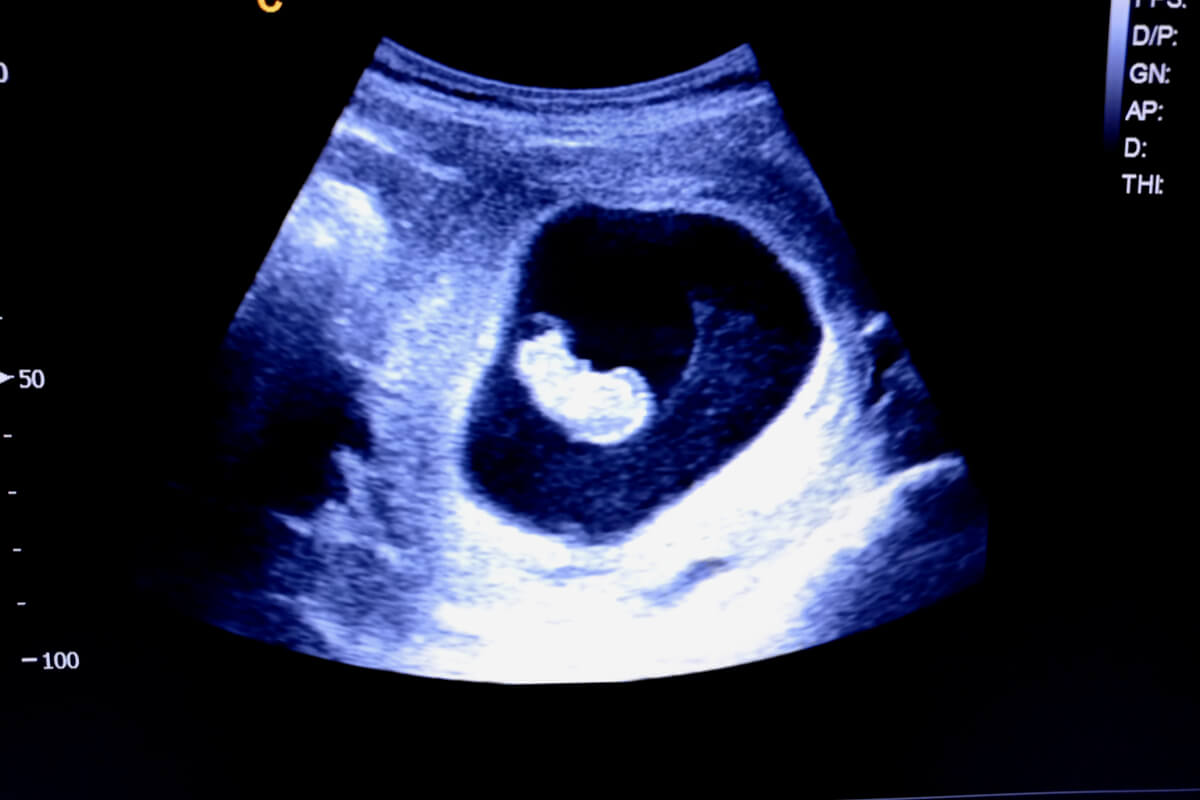

Este será más o menos el aspecto que tendrá tu bebé en una ecografía durante la semana 9 del embarazo: